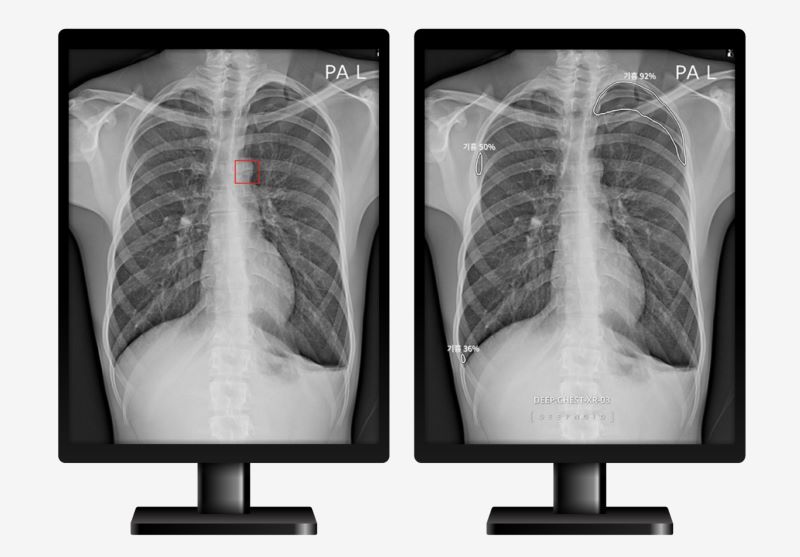

딥노이드 연구팀이 RSNA 2022에서 발표하는 논문은 네이처 파트너 저널(NPJ)에도 승인 받은 논문으로 AI가 의사를 도와 사람의 흉부 엑스레이(X-ray) 영상에서 이상 부위를 검출해 질환 진단 결정을 보조하는 딥체스트(DEEP:CHEST)를 고도화 시킨 AI 기반 흉부 영상진단서비스다.

이번 논문은 일반적인 질환 탐지뿐만 아니라 질환의 정확한 위치 정보까지도 진단결과에 포함했다. 또한 CAD 지원이 임상의의 진단성능에 미치는 영향을 추정하기 위해 별도의 시험을 진행했으며, 이를 통해 CAD를 사용했을 때의 임상의가 CAD를 사용하지 않았을 때에 비해 평균적으로 판독성능을 1.73배 개선했다는 결과를 보였다. 즉, 해당 CAD는 딥체스트의 높은 진단 성능을 보였을 뿐만 아니라, 임상 환경에서 임상의의 진단 성능에 긍정적인 영향을 미칠 수 있는 결과를 얻었다.

이번 논문을 기반으로 제품 고도화가 진행되어 흉부 엑스레이 영상에서 폐질환이 의심되는 부위와 위치까지 검출해 의사가 좀 더 빠르고 정확한 진단을 내릴 수 있게 되었다.